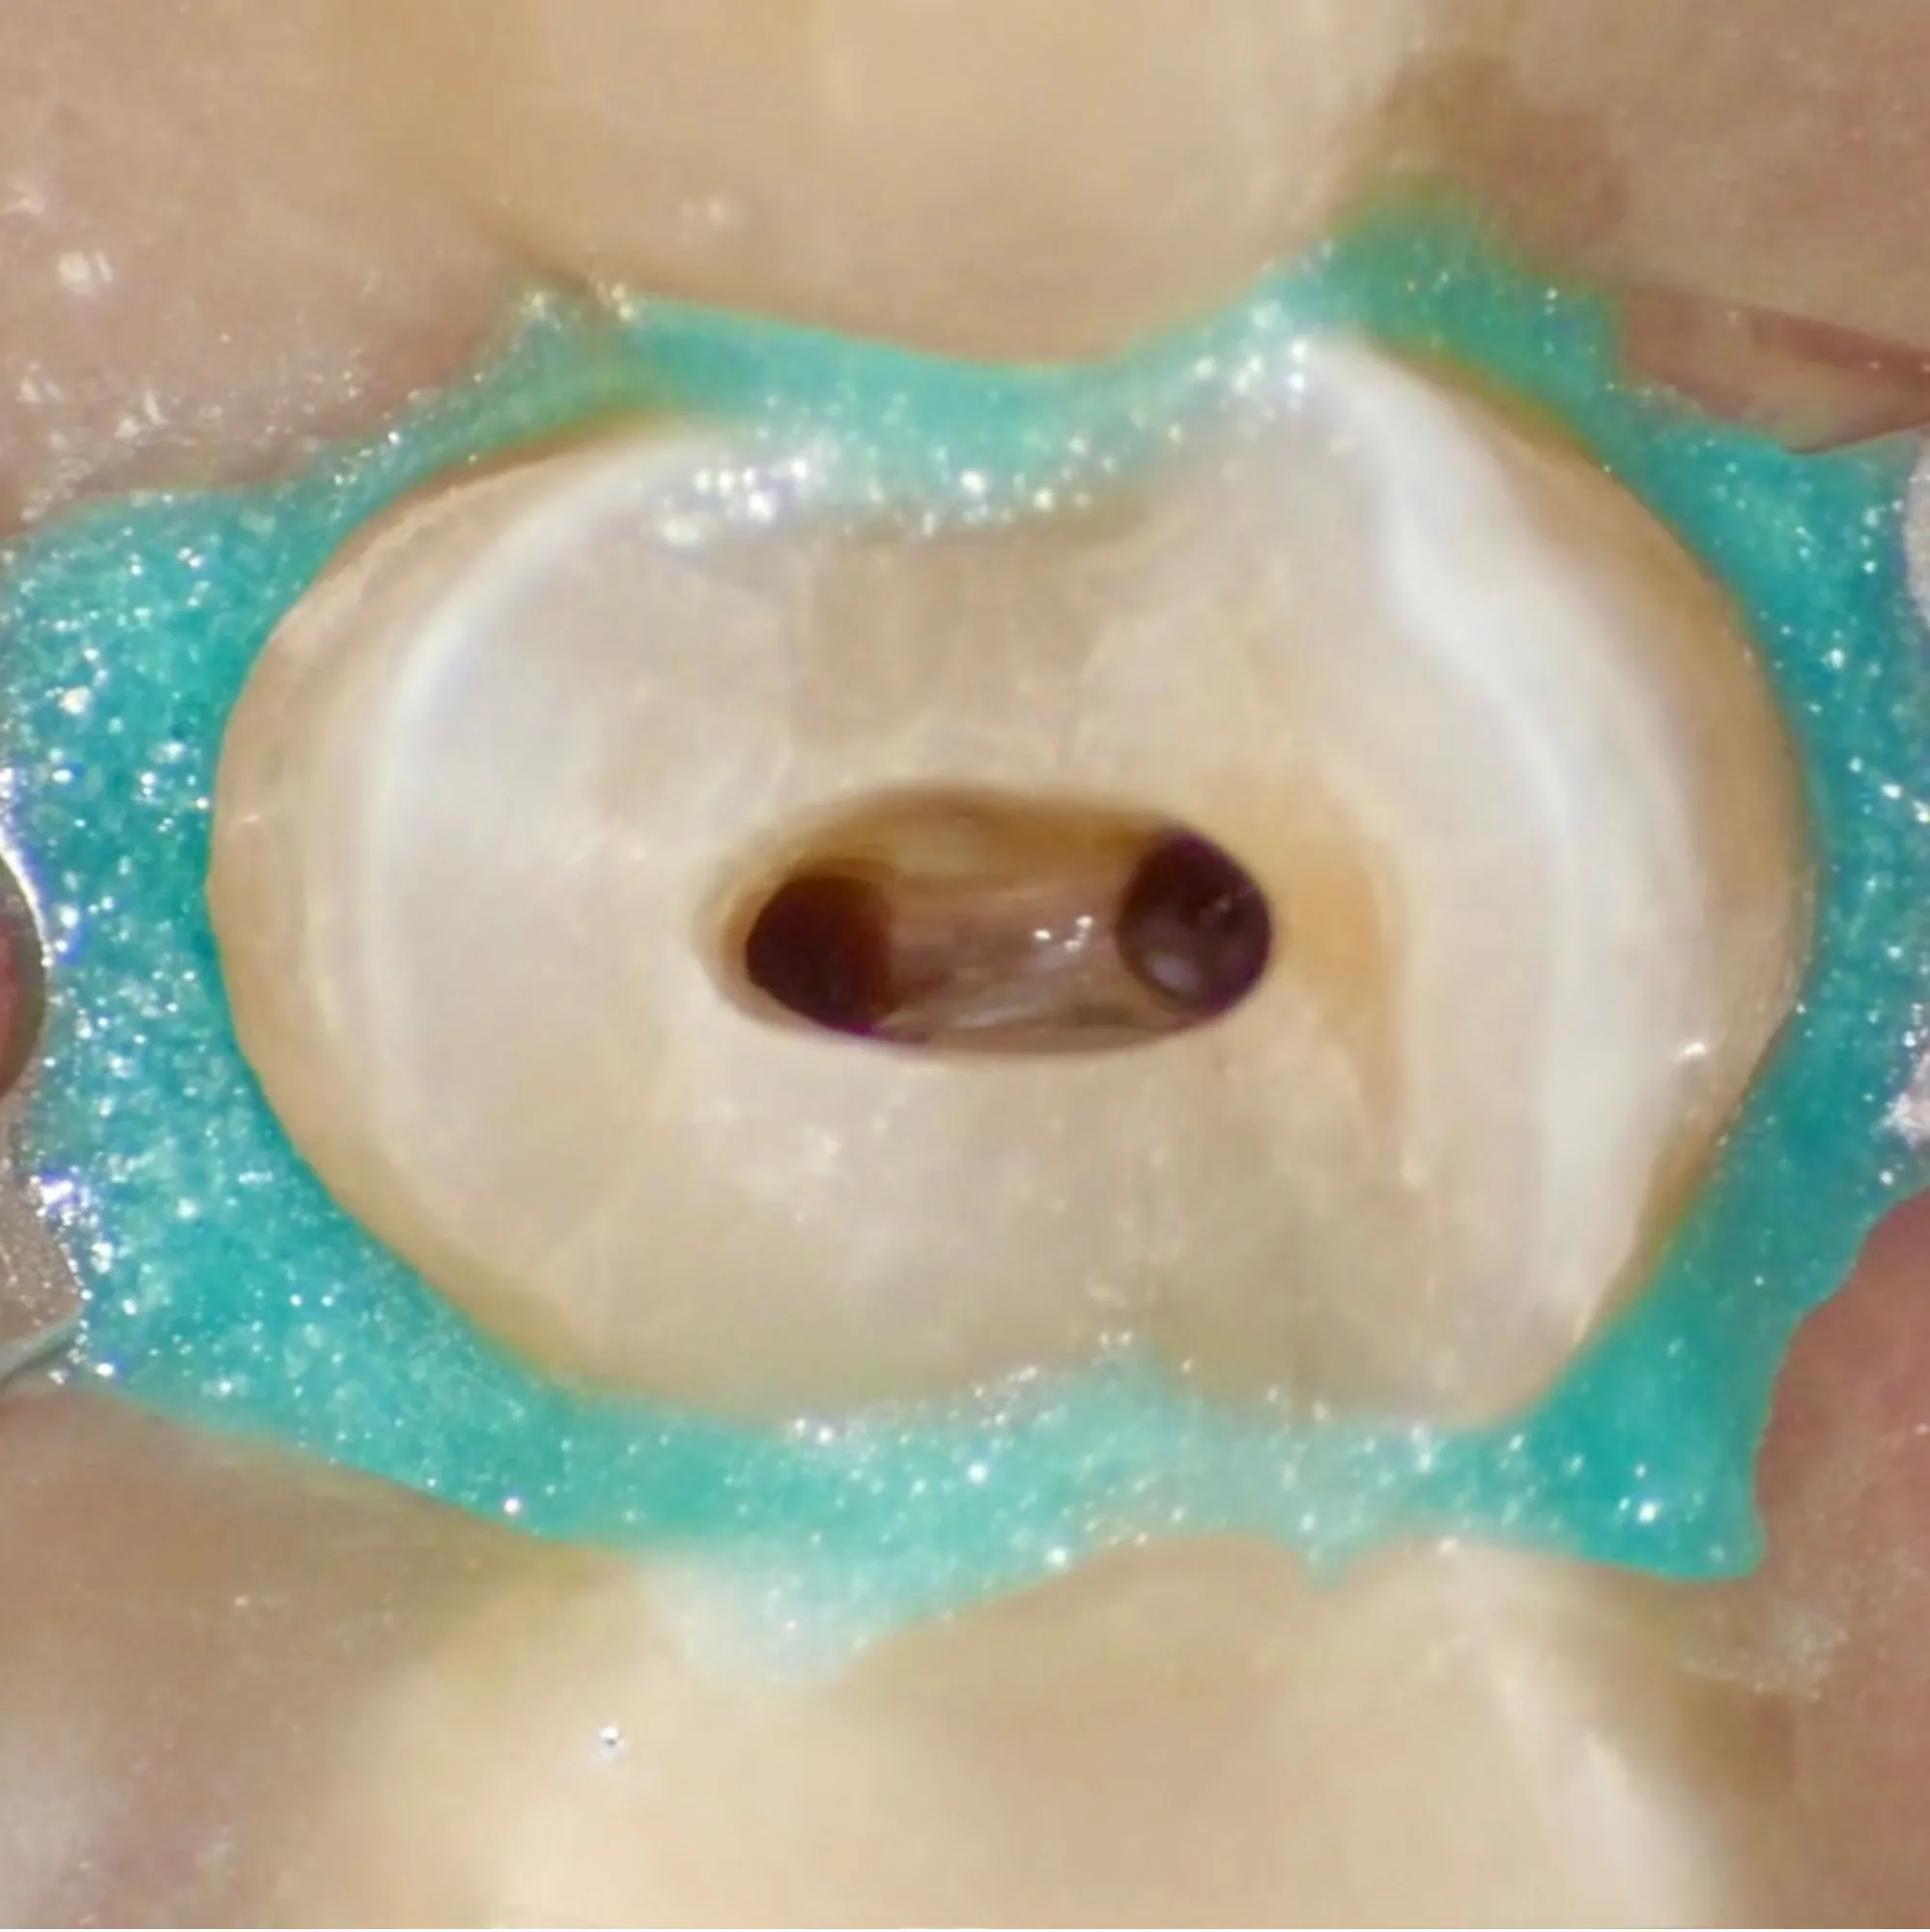

Endodonzia Ortograda

Fondamenti e tecniche avanzate dell'endodonzia ortograda moderna. Un corso completo che copre dalla diagnosi al trattamento.